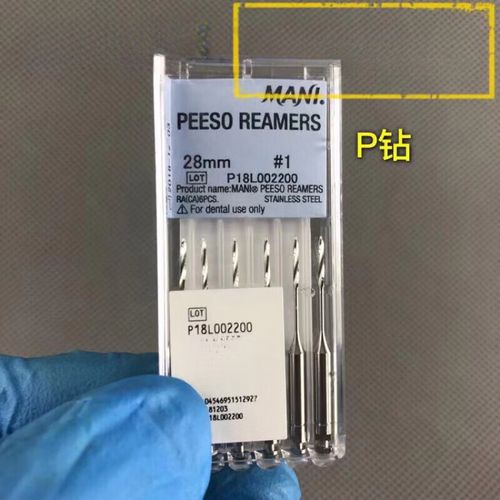

以下是牙科P钻的详细使用方法和注意事项:

- 选择合适尺寸和形态的P钻(不同直径、长度、锥度),根据龋坏范围、洞型大小和预备位置选择。

- 检查P钻:目视检查钻头是否有裂纹、崩刃、变形、柄部弯曲,用手触摸工作端是否光滑无毛刺。任何损坏的钻头都严禁使用!